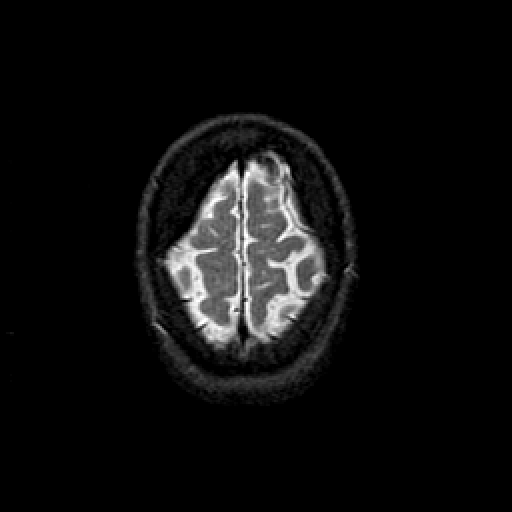

T2-weighted structural MR: Slice 47

Slice 47